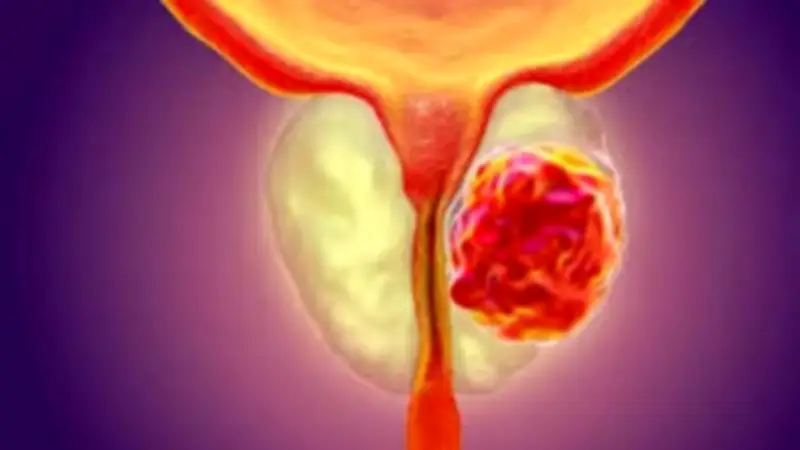

يُشخَّص أغلب الرجال بسرطان البروستاتا قبل ظهور الأعراض، إذ يتم اكتشاف نحو 85% من الحالات خلال الفحوصات المبكرة، قبل أن يشعر المريض بأي علامات واضحة. وقد يُظهر تحليل الدم ارتفاعًا غير طبيعي في مستويات مستضد البروستاتا النوعي (PSA)، أو يكتشف الطبيب تغيرات غير طبيعية أثناء الفحص الشرجي الروتيني.

أعراض سرطان البروستاتا

رغم أن العلامات المبكرة نادرة، فقد تظهر بعض الأعراض لدى بعض الرجال قبل التشخيص. وتعتمد شدة الأعراض على مكان الورم داخل البروستاتا ومدى تطوره، لكن وجود هذه الأعراض لا يعني بالضرورة الإصابة بسرطان البروستاتا.

إذا ترافق ألم العظام وتورم الساقين مع مشكلات بولية أو جنسية، فقد تكون هذه مؤشرات على مراحل متقدمة من سرطان البروستاتا. الفحوصات المبكرة قد تنقذ الحياة، لذلك لا تتجاهل العلامات التحذيرية.